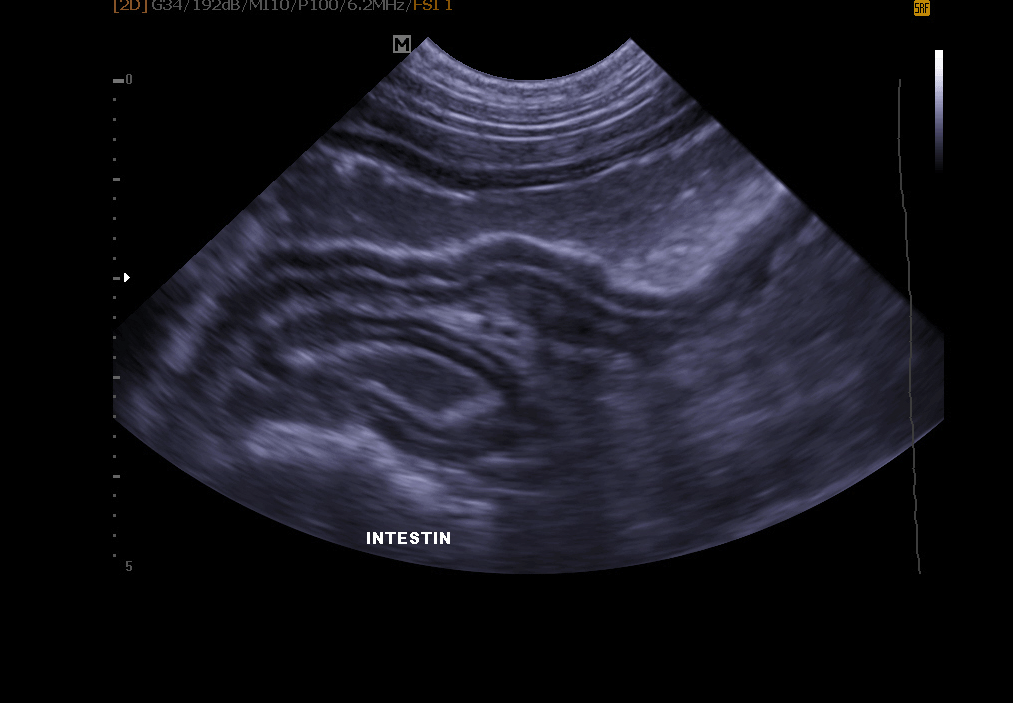

Echographie abdominale: elle permet l’exploration de le vessie (recherche de calculs, polypes, tumeur), des reins, de la rate , du foie , du pancréas et autres organes abdominaux.